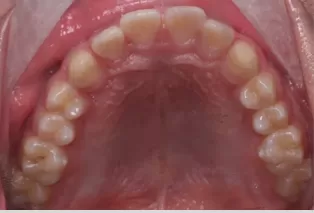

Photos intra-orales